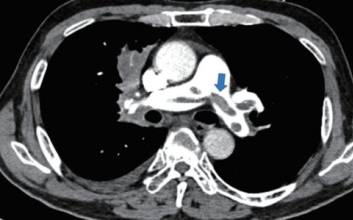

전 세계적으로 코로나19 백신(아스트라제네카)을 맞으면 혈전이 생길 수 있다는 우려가 크다. 다행히 세계보건기구(WHO)와 유럽의약품청(EMA)에 이어 우리나라 예방접종전문위원회(접종위)까지 백신과 혈전은 연관성이 없다는 결론을 내렸지만 우려가 완전히 사라지지 않았다. 일명 ‘피떡’으로 불리는 혈전의 치명성 때문이다. 혈전은 혈관 속에서 혈액이 굳어진 덩어리로, 혈류를 막아 생명까지 위협할 수 있다. 더구나 혈전은 혈전증을 비롯해 심혈관 및 뇌혈관 질환 등 다양한 중증 질환을 유발시키기도 한다. 순환기내과 전문의인 서울성모병원 장기육 교수는 “혈전증 환자는 폐동맥 색전증, 심혈관 및 뇌혈관의 색전이 발생할 위험성이 있다. 이런 질환으로 인해 오늘날까지도 사망에 이르는 환자가 많다”며 “혈관 내 혈전 발생이 치명적인 결과를 가지고 있다는 점을 늘 유의해야 한다”고 말했다. 그렇다고 겁먹거나 좌절할 건 아니다. 장기육 교수는 “의학의 발전으로 인해 혈전의 발생률은 인구학적인 변화에도 불구하고 대폭 늘어나지 않고 있고 사망률은 오히려 감소하고 있다”며 “신속한 진단과 치료, 적극적인 예방 활동으로 혈전증은 치료와 관리가 가능하다”고 말했다. 장기육 교수는 또 혈전증을 앓고 있는 환자의 경우 코로나19 백신 접종 시 신중을 기할 것을 당부했다. 장기육 교수에게 요즘 관심이 뜨거운 혈전에 대해 자세히 들어봤다. 치명적 질환 유발하는 혈전 - 최근 백신과 관련해 혈전 우려가 높다. 혈전은 그 자체로 위험한 것으로 안다. “혈전은 혈액 내의 섬유소와 혈소판이 엉겨 붙어 생기는 것으로, 피부가 베이거나 상처가 나서 대량 출혈이 발생하는 상황을 막아 준다. 그러나 혈관 안에서 형성됐을 때는 스스로 녹는 경우가 많지 않으며, 혈액의 흐름에 따라 먼 곳의 혈관을 막아 조직이나 장기의 경색을 일으켜 위험한 상황을 초래할 수 있다.” - 혈전은 다른 질환을 일으키기도 한다는데. “혈전이 사람의 정맥에서 발생했을 때 심부정맥 혈전증이라고 한다. 혈전증 중 가장 흔하며, 초기에는 정맥이 확장되고 꼬부라지는 정맥류가 나타나고, 증상이 심해지면 다리가 붓고, 피부 변색이 생기며, 궤양이 발생한다. 또 이 심부정맥 혈전이 떨어져 나가 폐혈관을 막는 폐동맥 색전증이 발생하는데, 폐혈관 색전의 범위와 우심실 기능을 어느 정도 저하시키는지에 따라 치명적일 수 있다. 적절하게 치료받지 못한 급성 폐동맥 색전증의 경우 30% 정도가 사망한다고 보고되고 있다. 이외에도 심장의 관상동맥, 뇌혈관 등에 색전증이 생기는 경우 치명적인 경과를 밟는 경우가 많다.” - 혈전증을 얘기할 때 색전증이 꼭 언급된다. “색전은 혈전이 발생한 위치에서 이동하지 않고 제자리를 지키다가 특정 원인으로 인해 제 위치에서 떨어져 혈액의 흐름에 따라 날아간 것을 말한다. 이런 색전은 말단의 혈관을 막아 조직이나 장기의 혈액 순환을 방해하며, 혈관을 막지 않는다고 해도 다시 떨어져 나갈 위험성이 아주 높다.” - 백신과 관련해 파종성 혈관내 응고장애와 뇌정맥동 혈전증에 대한 우려가 제기됐다. “파종성 혈관내 응고장애, 혹은 범발성 혈관내 응고장애는 특정한 원인으로 인해 혈관 내 지혈을 담당하는 성분이 과도하게 활성화돼 여러 조직과 장기에 다발성 응고를 일으키는 상태를 말한다. 이로 인해 지혈과 응고를 담당하는 성분이 과하게 소모되면 정상적으로 응고 작용이 일어나야 할 곳에서 응고가 일어나지 못하고 출혈 상태가 지속해 결과적으로는 응고와 출혈이 동시에 발생한다. 주로 패혈증, 중증 외상, 종양, 수술 전후로 나타나며 임신과 분만 시에도 나타날 수 있는 합병증이다. 파종성 혈관내 응고장애는 사망률이 20%에서 50%까지 이를 정도로 한 번 발생하면 치명적인 경과를 보이는 경우가 많다. 뇌정맥동 혈전증은 머리뼈 안에 있고 안구 뒤에 있는 ‘뇌정맥동’이라고 하는 정맥 혈관에 혈전이 발생하는 상태를 말한다. 안면부나 구강의 감염으로 인해 발생하는 경우가 많은 것으로 알려져 있고, 심한 두통으로 시작해 발적·발열부터 의식저하·경련·사망 등까지 이를 수 있다. 사망률이 30% 내외로 보고되는 드물지만 발생하면 치명적이다.” - 혈전증 환자가 코로나19 백신을 맞는 것은 괜찮나. “현재까지는 일부 코로나 19 백신 접종과 혈전증 발생의 유의한 연관성이 입증된 것은 아니다. 그러나 이전에 혈전증을 앓은 적이 있거나 치료 중인 사람, 고령의 노인 등 혈전증 발생의 고위험군에서는 백신 접종에 대해 좀 더 신중을 기하는 것이 적절할 것으로 생각된다.” 젊고 건강해도 혈전 생겨…치료·관리 가능 - 방역 당국은 신부정맥 혈전증이나 폐색전증 등의 혈전 생성은 비교적 흔한 질병이라고 하는데…. “혈전은 기저 질환이 있는 환자에서 생기는 경우가 많지만, 평소 건강했던 성인에서도 장기간의 여행 등으로 인한 움직임 저하, 탈수, 중증 외상 등으로 인해서도 생길 수 있다.” - 혈전 발생 위험이 높은 경우는. “혈관 내 손상이 있을 때, 혈액의 정체가 있을 때, 응고 과다 상태일 때 더 잘 엉겨 붙게 된다. 또 혈전은 나이가 들수록 발생하는 빈도가 증가하고, 과거에 혈전으로 치료받은 과거력이 있거나 가족력이 있는 사람에서도 혈전의 위험성이 높다. 비만·장거리 여행·부동성 등과 같은 상태에서도 증가하며, 감염·수술·악성 종양과 같은 상태나 질환에서도 혈전의 발생 위험이 증가한다.” - 의외로 혈전증 환자가 많지 않다. “혈전을 조기에 발견할 수 있는 진단 기술이 발전했을 뿐만 아니라 비만 인구의 증가, 인구의 고령화 등으로 인해 혈전증 환자가 증가하는 요인도 있다. 그러나 그에 맞춰 혈전 발생에 대한 의료진의 관심 증대 등으로 인해 혈전증 환자가 실제로 많이 증가하는 것은 아니다. 또 혈전으로 인한 사망률은 이전보다 많이 감소한 것으로 나타나고 있다. 그래도 혈관 내 혈전 발생이 치명적인 결과를 가져올 수 있다는 점을 늘 유의해야 한다.” - 혈전증은 치료와 관리가 가능한 질환이라고 하는데. “신속한 진단과 치료, 적극적인 예방 활동으로 혈전증은 치료와 관리가 가능하다. 혈압과 맥박 등의 활력 징후(vital sign)가 불안정한 환자에서는 혈전 및 색전을 녹이는 혈전용해술이 시행되며, 그렇지 않은 환자에서는 항응고 치료를 시행하게 된다. 또 심부정맥 혈전증이 여러 차례 재발하는 환자에서는 정맥 내 혈전이 발생할 경우 혈전이 심장 및 폐동맥으로 들어가지 않도록 걸러 주는 필터(IVC filter)를 삽입해 폐혈전 색전증으로 인한 위험을 예방할 수 있다.” - 혈전약은 평생 먹어야 하는 것으로 안다. 부작용은. “혈전 환자는 경우에 따라 일정 기간 항응고제를 복용해야 하며, 환자의 발생 위험도에 따라 평생 약을 먹는 경우도 있다. 이런 약제는 혈액의 응고 작용을 방해해 상대적으로 출혈이 발생할 가능성이 커진다. 사소한 외상에도 멍이 잘 들거나 칫솔질 후 잇몸에서 피가 자주 나는 등의 출혈이 발생할 수 있어 주의를 요한다.” 출혈 조심 또 조심…누워 있는 시간 줄여라 - 혈전증 환자가 가장 조심해야 하는 것은. “항응고제를 복용하게 되면 출혈의 위험성이 증가한다. 특히 수술이나 시술, 조직검사를 받을 때 항응고제를 복용 중인 분은 의료진이 사전에 인지하지 못하는 경우 치명적인 출혈로 이어질 수 있다. 담당 의사와 상의해 수술이나 시술, 검사를 받도록 하는 것이 중요하다.” - 평소 혈전 예방은 어떻게 해야 하나. “질병이 있거나 수술 이후라도 가능하면 누워 있는 시간을 줄이고 활동 시간을 늘리는 것이 좋다. 불가피하게 오랜 시간 누워 있어야 하는 경우에도 자주 다리를 움직여 주도록 하고, 장시간 동안 비행이나 차량 탑승을 해야 하는 경우에도 정기적으로 다리를 움직이고 스트레칭을 하는 것이 중요하다.” - 혈전에 대해 사람들이 가장 잘못 알고 있는 것은. “혈전은 나이가 많은 사람에게서만 생기는 것으로 알 수도 있으나, 실제로는 젊은 사람에서도 탈수, 외상, 오랜 기간의 부동자세, 장거리 여행, 경구 피임약 사용 등의 위험인자들이 동반된 경우에서도 발생할 수 있다. 하지 통증 및 부종, 호흡곤란 등의 증상이 있어 혈전증이 의심되는 경우 진료를 받아 보기 권한다.” 권오용 기자 kwon.ohyong@joongang.co.kr 2021.03.30 07:00